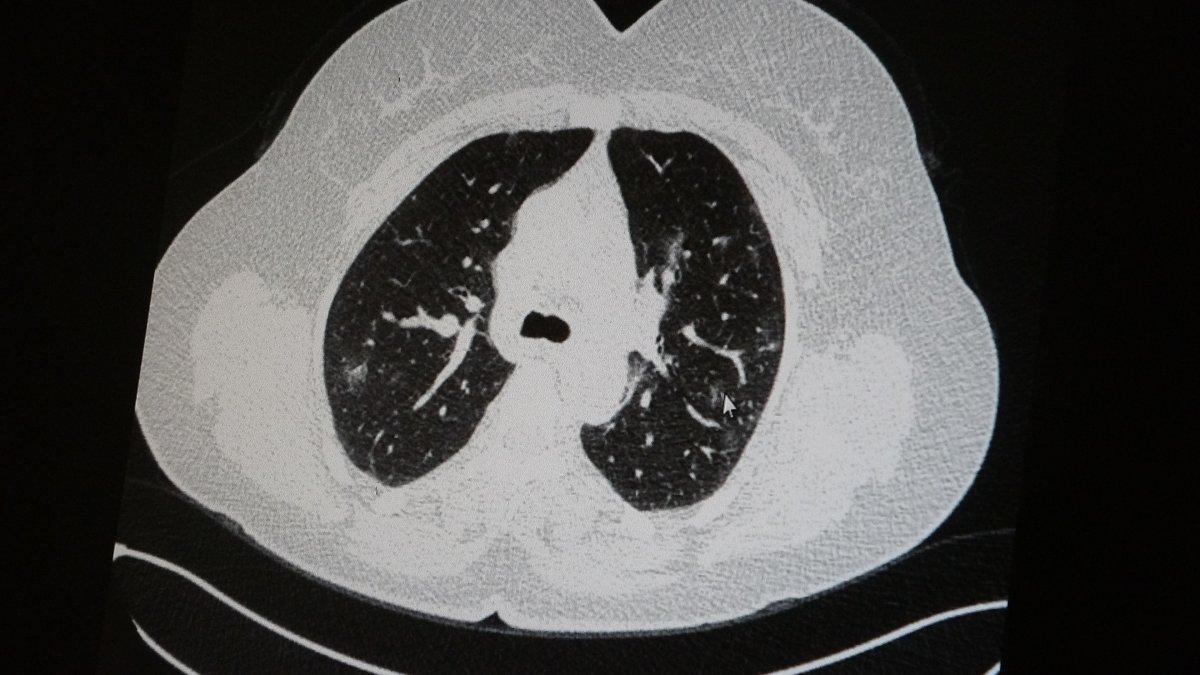

Azar, aynı şekilde aşı olup koronavirüs hastalığına yakalanan bir başka genç hastanın akciğer tomografisinde herhangi bir sorunun olmadığını ve hastanın durumunun iyi olduğunu gözlemlediklerini kaydetti.